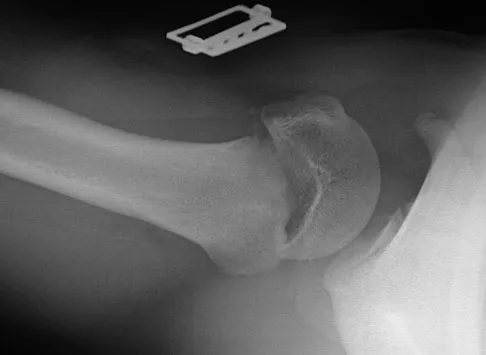

A patient with rheumatoid arthritis with both ankle and subtalar involvement was treated as shown in Figures 11a and 11b. What complication is unique to this type of fixation?

Explanation

The interlocking screws at the proximal end of the rod can act as a stress riser and lead to fracture. Postoperative pain at this level should prompt inclusion of this diagnosis in the differential. Removing the screws following bone union can decrease the chances of this occurring. A short rod that avoids the diaphyseal area may also be beneficial. Rotatory deformity is controlled by the perpendicularly oriented distal transfixion screws. Talar osteonecrosis would be unusual since the dissection can be minimized with an intramedullary rod. Any type of hardware can fail if the construct does not lead to a solid arthrodesis. Nunley JA, Pfeffer GB, Sanders RW, et al (eds): Advanced Reconstruction: Foot and Ankle. Rosemont, IL, American Academy of Orthopaedic Surgeons, 2004, pp 236-237. Thordarson DB, Chang D: Stress fractures and tibial cortical hypertrophy after tibiotalocalcaneal arthrodesis with an intramedullary nail. Foot Ankle Int 1999;20:497-500.